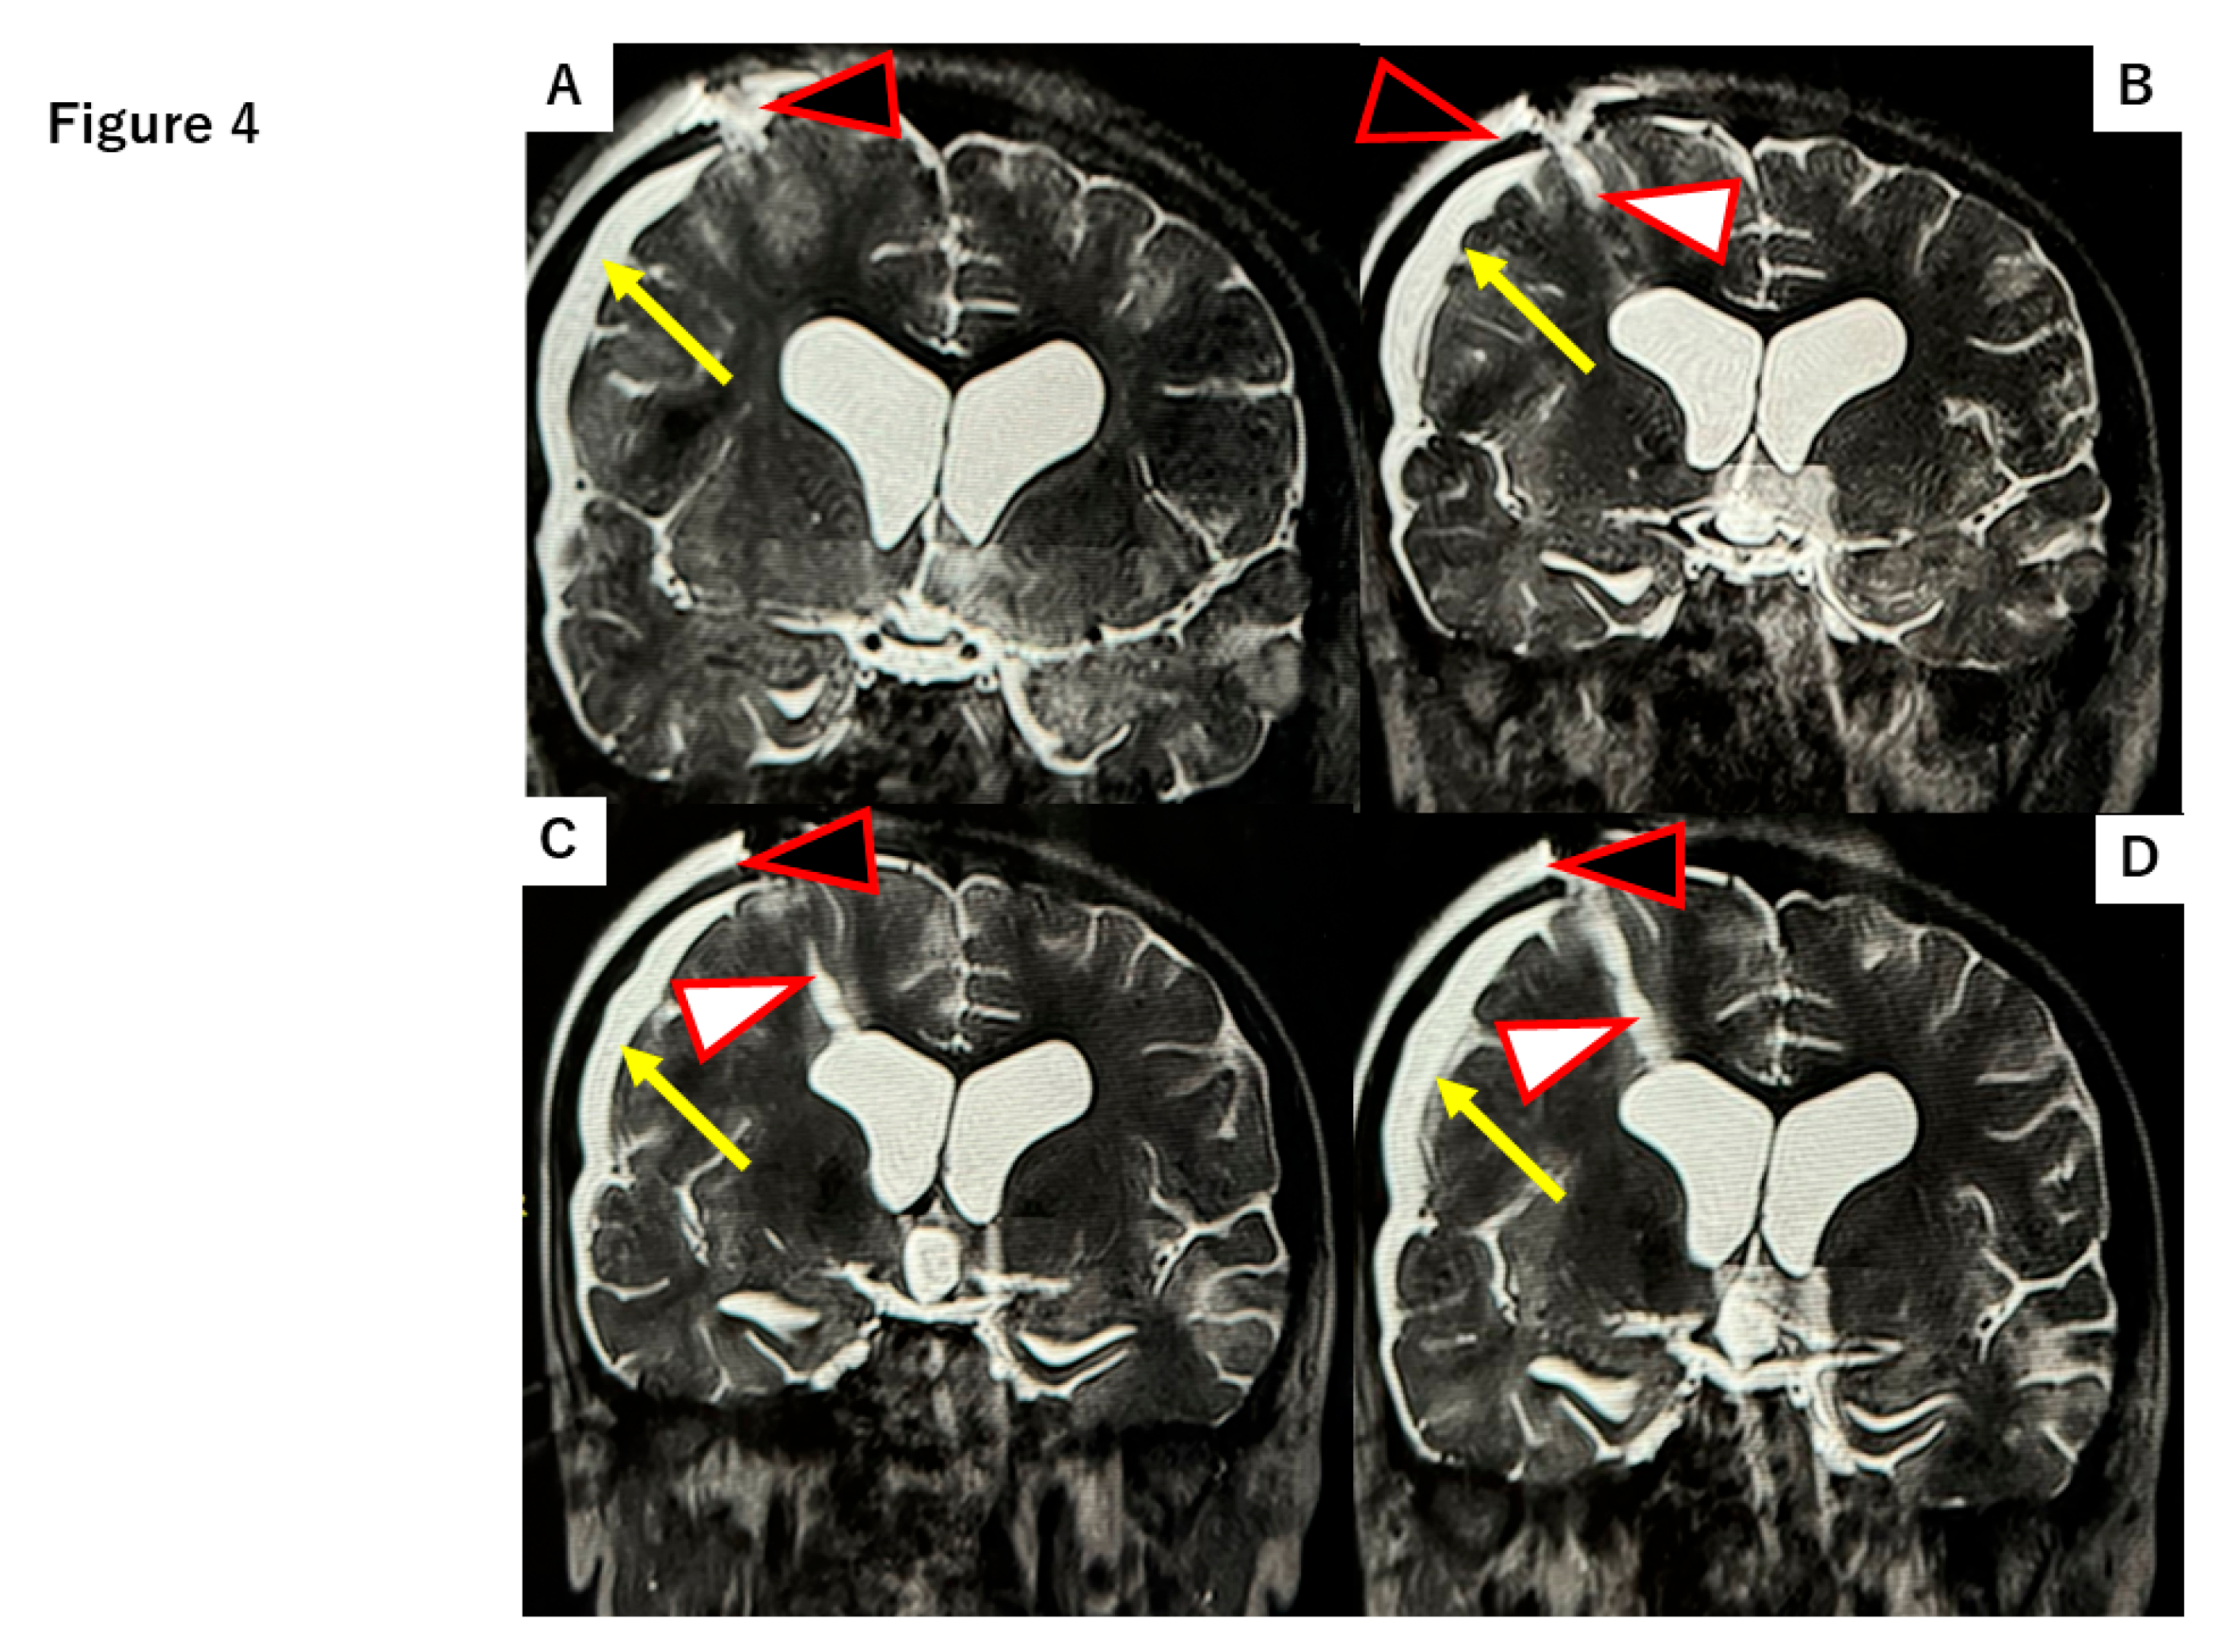

Several reports have described the use of parenchymal “plugs,” such as oxidized regenerated cellulose (Surgicel®; Ethicon, Inc., Bridgewater, NJ, USA) or gelatin sponge (Gelfoam®; Pfizer), to fill brain parenchymal defects [7,8]. In this case, we had the opportunity to compare the performance of Surgicel versus DuraGen in preventing CSF leaks and promoting healing, as observed on serial postoperative MRIs. Use of Surgicel was associated with persistent subdural hygroma (fluid collection) and subcutaneous fluid accumulation. In a patient where Surgicel was used to pack the NeuroPort tract, the pathway through the brain parenchyma remained as a fluid-filled defect one month postoperatively, as shown in Figure 4, In the same case, the tract had not healed even two years postoperatively (Figure 4).

Figure 4. T2-weighted MR images at 30 days and two years postoperative in a case where Surgicel® was used to pack the NeuroPort tract (with schematic diagram inset). (A-C) Along with the NeuroPort tract, a persistent fluid-filled parenchymal defect (white arrowhead) is visible at 30 days post-op, with reflux of CSF back into the ventricular system. This is associated with the formation of a subdural hygroma (yellow arrow). CSF accumulation is also evident in the subcutaneous tissue (effusion from the dural defect, black arrowhead). (D) Little to no healing of the tract is observed even at two years follow-up.